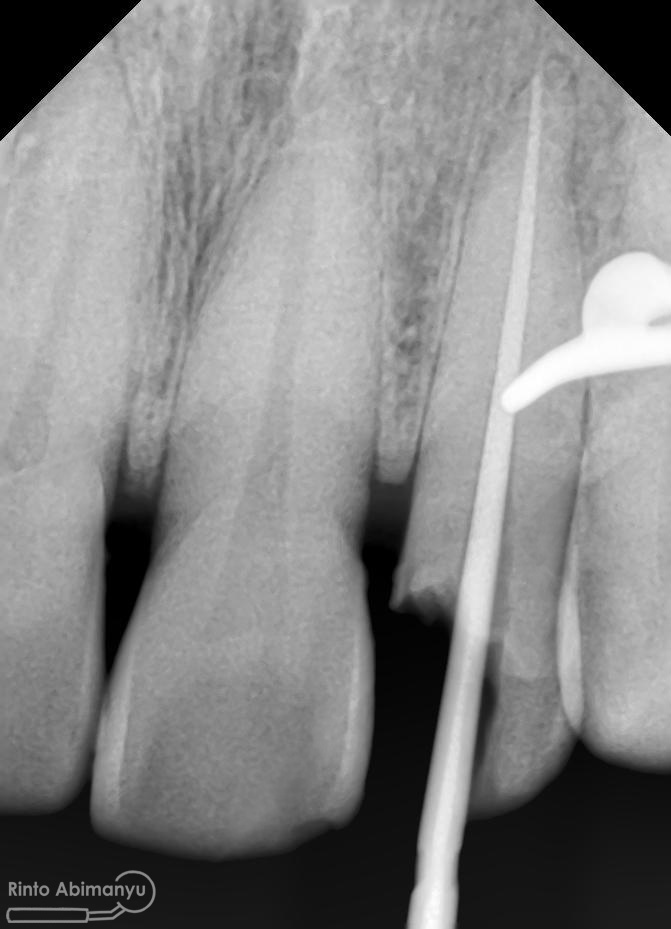

Setelah proses cleaning and shaping dilakukan trial gutta percha untuk melihat apakah kon utama yang akan kita gunakan pas dengan saluran akarnya…

Setelah melihat hasil ronsen trial guttap maka pengisian siap dilakukan… Untuk pengisian saluran akar saya memakai tehnik warm vertival condensation memakai alat Element Obturation Unit (SybronEndo) dan siler AH plus (Dentsply)…